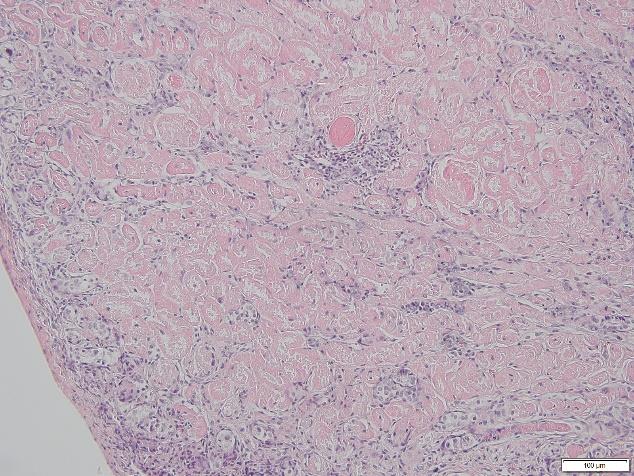

Images were taken on the microscope of the IRI kidneys I stained. Histological features such as protein casts and necrotic tubular cells can be seen which indicate injury due to induced IRI.